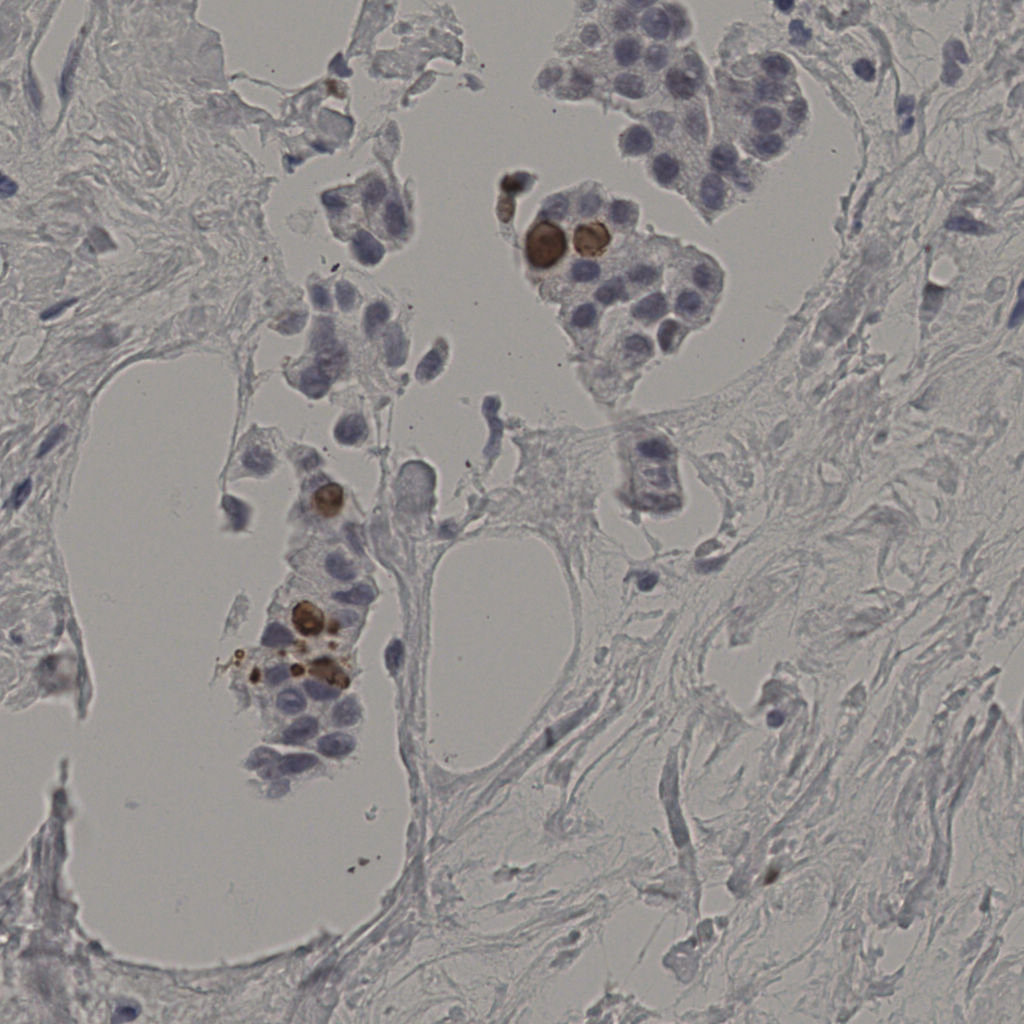

5.31%

Ki67 指数

阴 19502 阳 1093